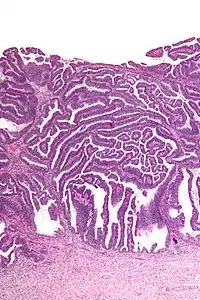

Micrograph of a villoglandular adenocarcinoma the cervix. H&E stain.

The name of the lesion describes it microscopic appearance. It has nipple-like structures with fibrovascular cores (papillae) that are long in relation to their width (villus-like), which are covered with a glandular pseudostratified columnar epithelium.